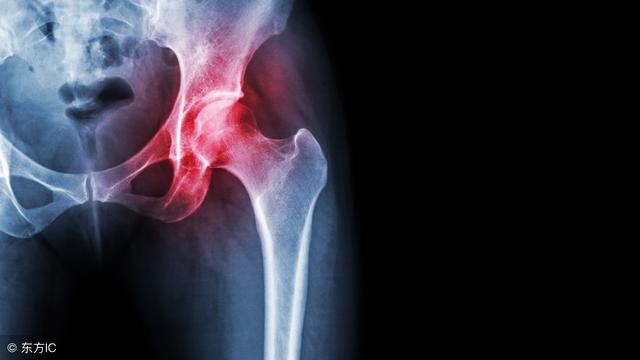

3、股骨 头病变

对于一些不明原因的腰腿痛,如果排除了常见的腰椎间盘突出及腰椎压缩性骨折,我们可能还需要排除患者的股骨头是否存在病变。由于下肢神经的连续性,常常导致股骨头病变的患者出现膝盖的疼痛,甚至整个下肢的疼痛,有时候疼痛会波及腰部,老人家有时候又说不清楚到底是腰先痛的还是腿先痛的!

对于这里所说的股骨头病变一般是指股骨头坏死引起来的,对于股骨头坏死的治疗需要结合坏死的分期给予一定治疗:早期:减少负重,口服非甾体消炎药,可以做做高压氧治疗,避免股骨头缺血坏死加重;后期:股骨头塌陷了,口服药物无法止痛,那可能就要做关节置换手术了!